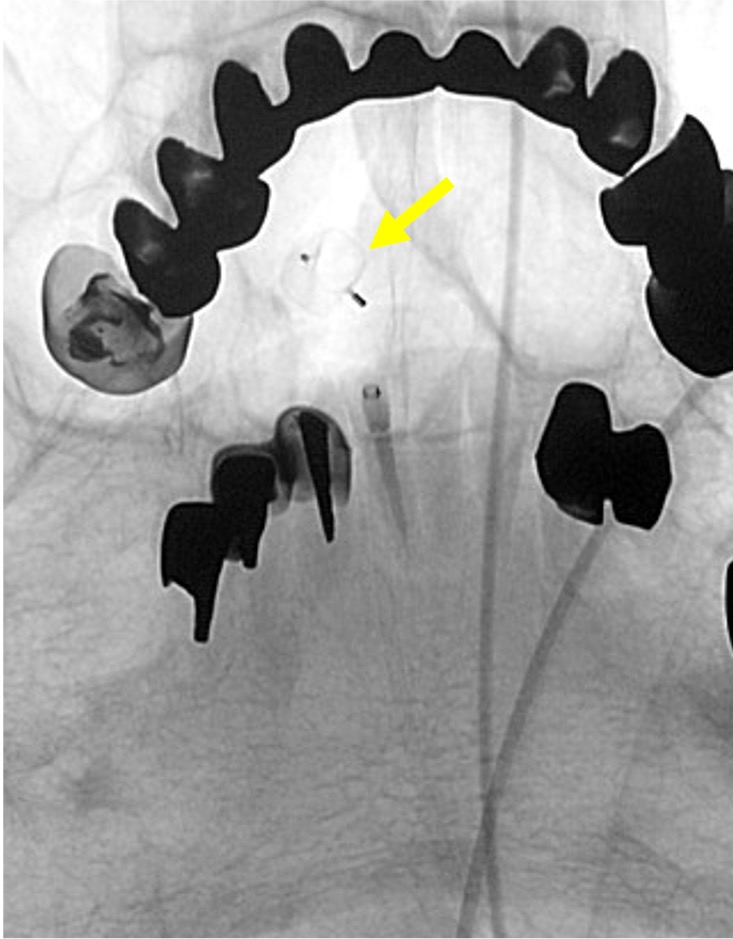

当院で行われた症例を提示いたします。80歳、女性、くも膜下出血の患者様。血管撮影にて図1〜4赤矢印の様に脳底動脈に広頸のネックを伴う不整形の瘤を認めました。母血管の蛇行狭窄が強く、マイクロカテーテルが複数入りにくい状態だったのでWEB(図5〜8黄色矢印)を用いて治療を行いました。術後MRAでも図10青矢印の様に動脈瘤は描出されません(図9は術前MRA)。現在も出血なく経過しております。

図5 |